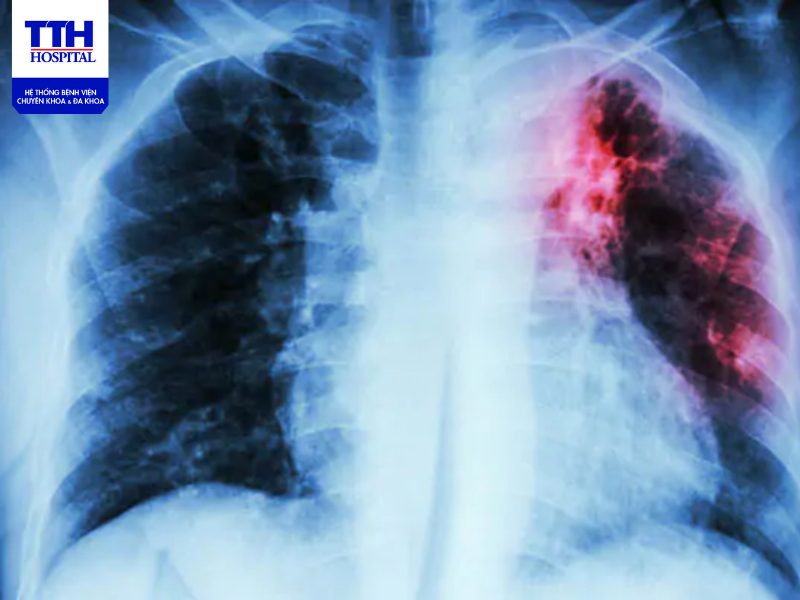

- Chụp X-quang phổi để nhận biết rõ các biểu hiện của bệnh lao thể hiện trên phim.

Khi nghi ngờ mắc lao, người bệnh sẽ được cho thực hiện các phương pháp sau để chẩn đoán gồm có: